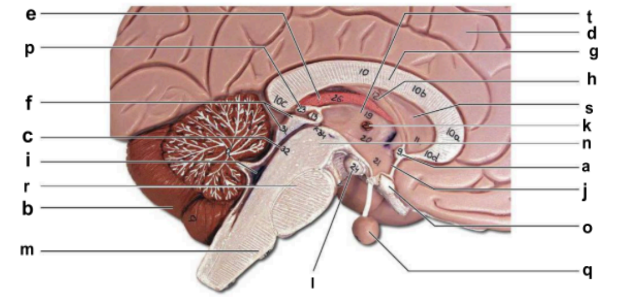

Identify the structure labeled “a” in the image.

anterior commissure

Identify the structure labeled “b” in the image.

cerebellum

Identify the structure labeled “c” in the image.

cerebral aqueduct

Identify the structure labeled “d” in the image.

cerebral hemisphere

Identify the structure labeled “e” in the image.

choroid plexus

Identify the structure labeled “f” in the image.

corpora quadrigemina

Identify the structure labeled “g” in the image.

corpos callosum

Identify the structure labeled “h” in the image.

fornix

Identify the structure labeled “i” in the image.

fourth ventricle

Identify the structure labeled “j” in the image.

hypothalamus

Identify the structure labeled “k” in the image.

interthalamic adhesion

Identify the structure labeled “l” in the image.

mammilary body

Identify the structure labeled “m” in the image.

medulla oblongata

Identify the structure labeled “n” in the image.

midbrain

Identify the structure labeled “o” in the image.

optic chiasma

Identify the structure labeled “p” in the image.

pineal gland

Identify the structure labeled “q” in the image.

pituitary gland

Identify the structure labeled “r” in the image.

pons

Identify the structure labeled “s” in the image.

septum pellucidum

Identify the structure labeled “t” in the image.

thalamus